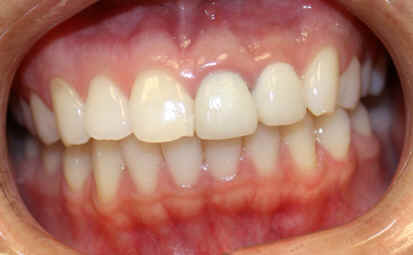

23 year-old female, "I want braces"

Dental history: #9 fracture at age of 8; #9,10 crowns (joined) 2 years ago; #9 has chronic apical infection, #19 extracted due to caries at age of 15